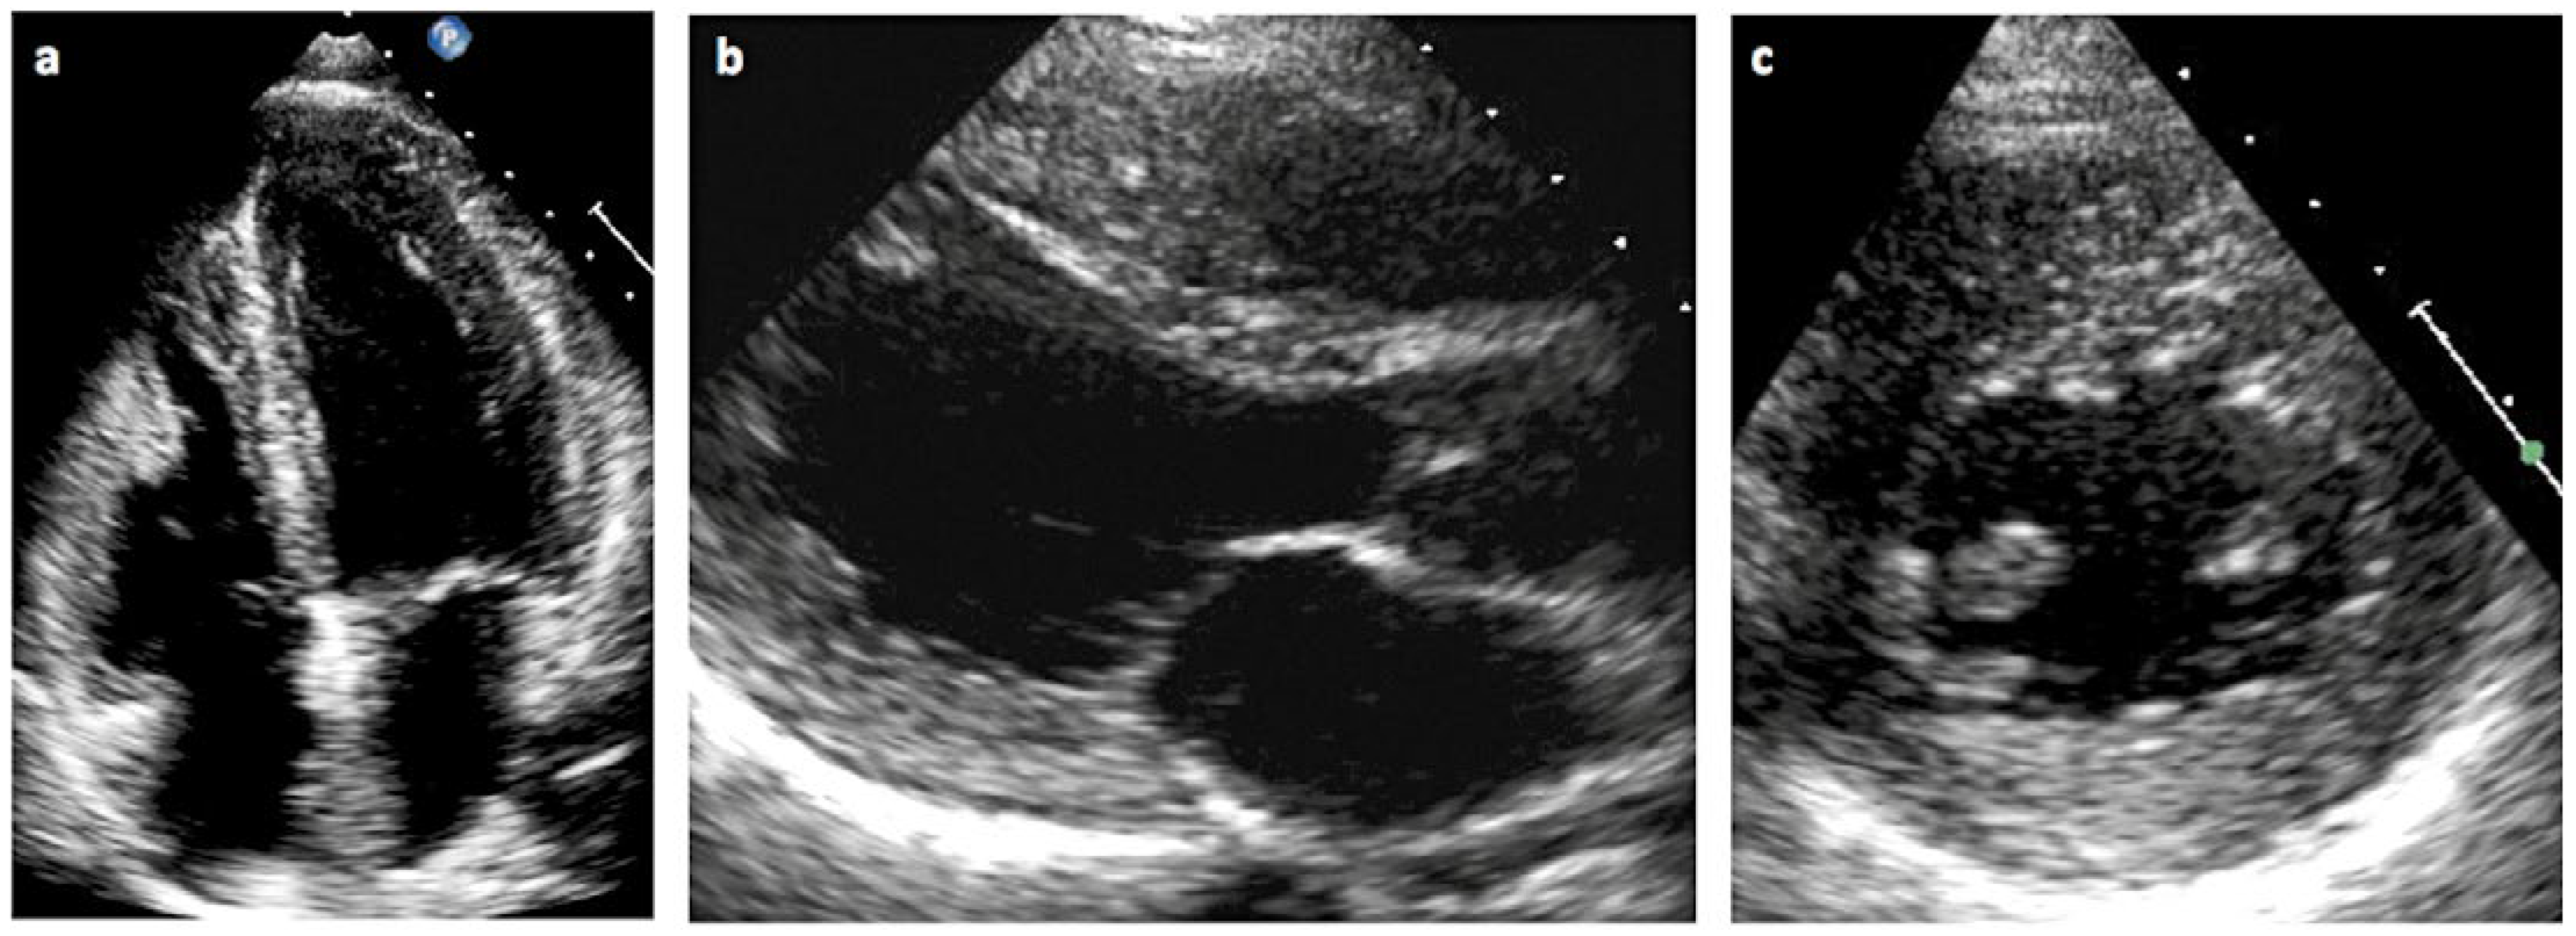

Wie manifestiert sich die Kardiomyopathie beim Morbus Fabry?

- Charakteristische EKG-Veränderungen und/oder echokardiografische veränderungen im Sinne einer linksventrikulären Hypertrophie können Manifestationen eines Morbus Fabry sein.